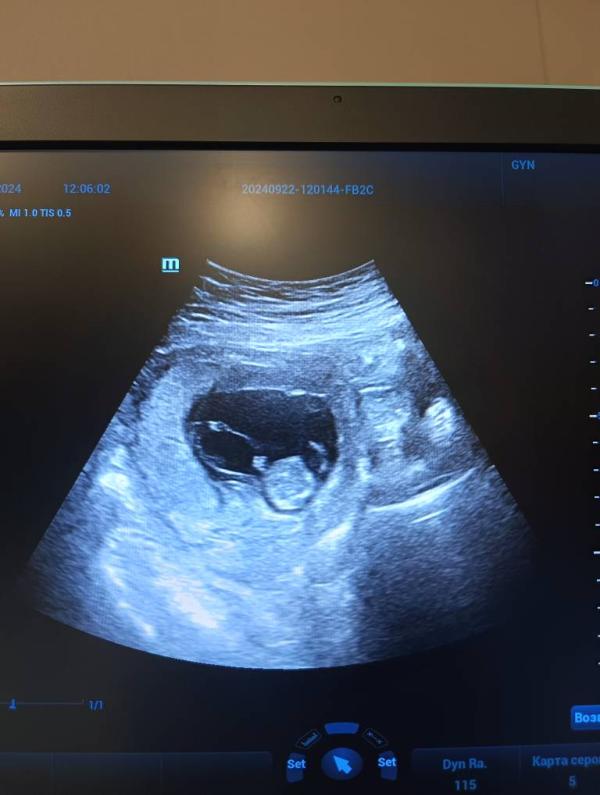

Узи не в скрининговые сроки

Такое УЗИ можно проводить в любом сроке беременности.

Процедура включает в себя:

✔️Определение положения плода

✔️ Расчет ПМП (предполагаемой массы плода)

✔️ Оценка сердцебиения и кровотока плода

✔️ Оценка количества околоплодных вод

✔️ Оценка плаценты

✔️ Состояние шейки матки

Так же вы можете попросить доктора посмотреть пол вашего малыша🫶🏻